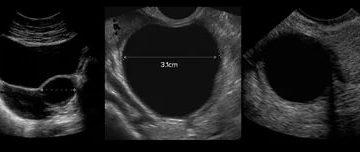

Киста яичника на УЗИ Яичники — это парные органы, имеющие огромное значение при зачатии. Именно…